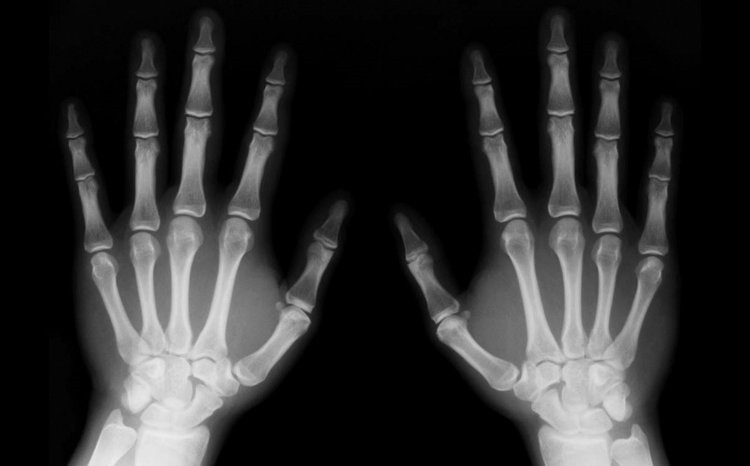

Rayos X

Los rayos X tienen longitudes de onda mas larga que los rayos gamma, pero menores que la radiación ultravioleta, y por lo tanto, su energía es mayor que la de estos últimos.

Se utilizan en diversas aplicaciones científicas e industriales, pero principalmente en medicina, como en el caso de las radiografías.

radiografia - Rayos X

Los rayos X son emitidos por electrones del exterior del núcleo, mientras que los rayos gamma son emitidos por el núcleo.